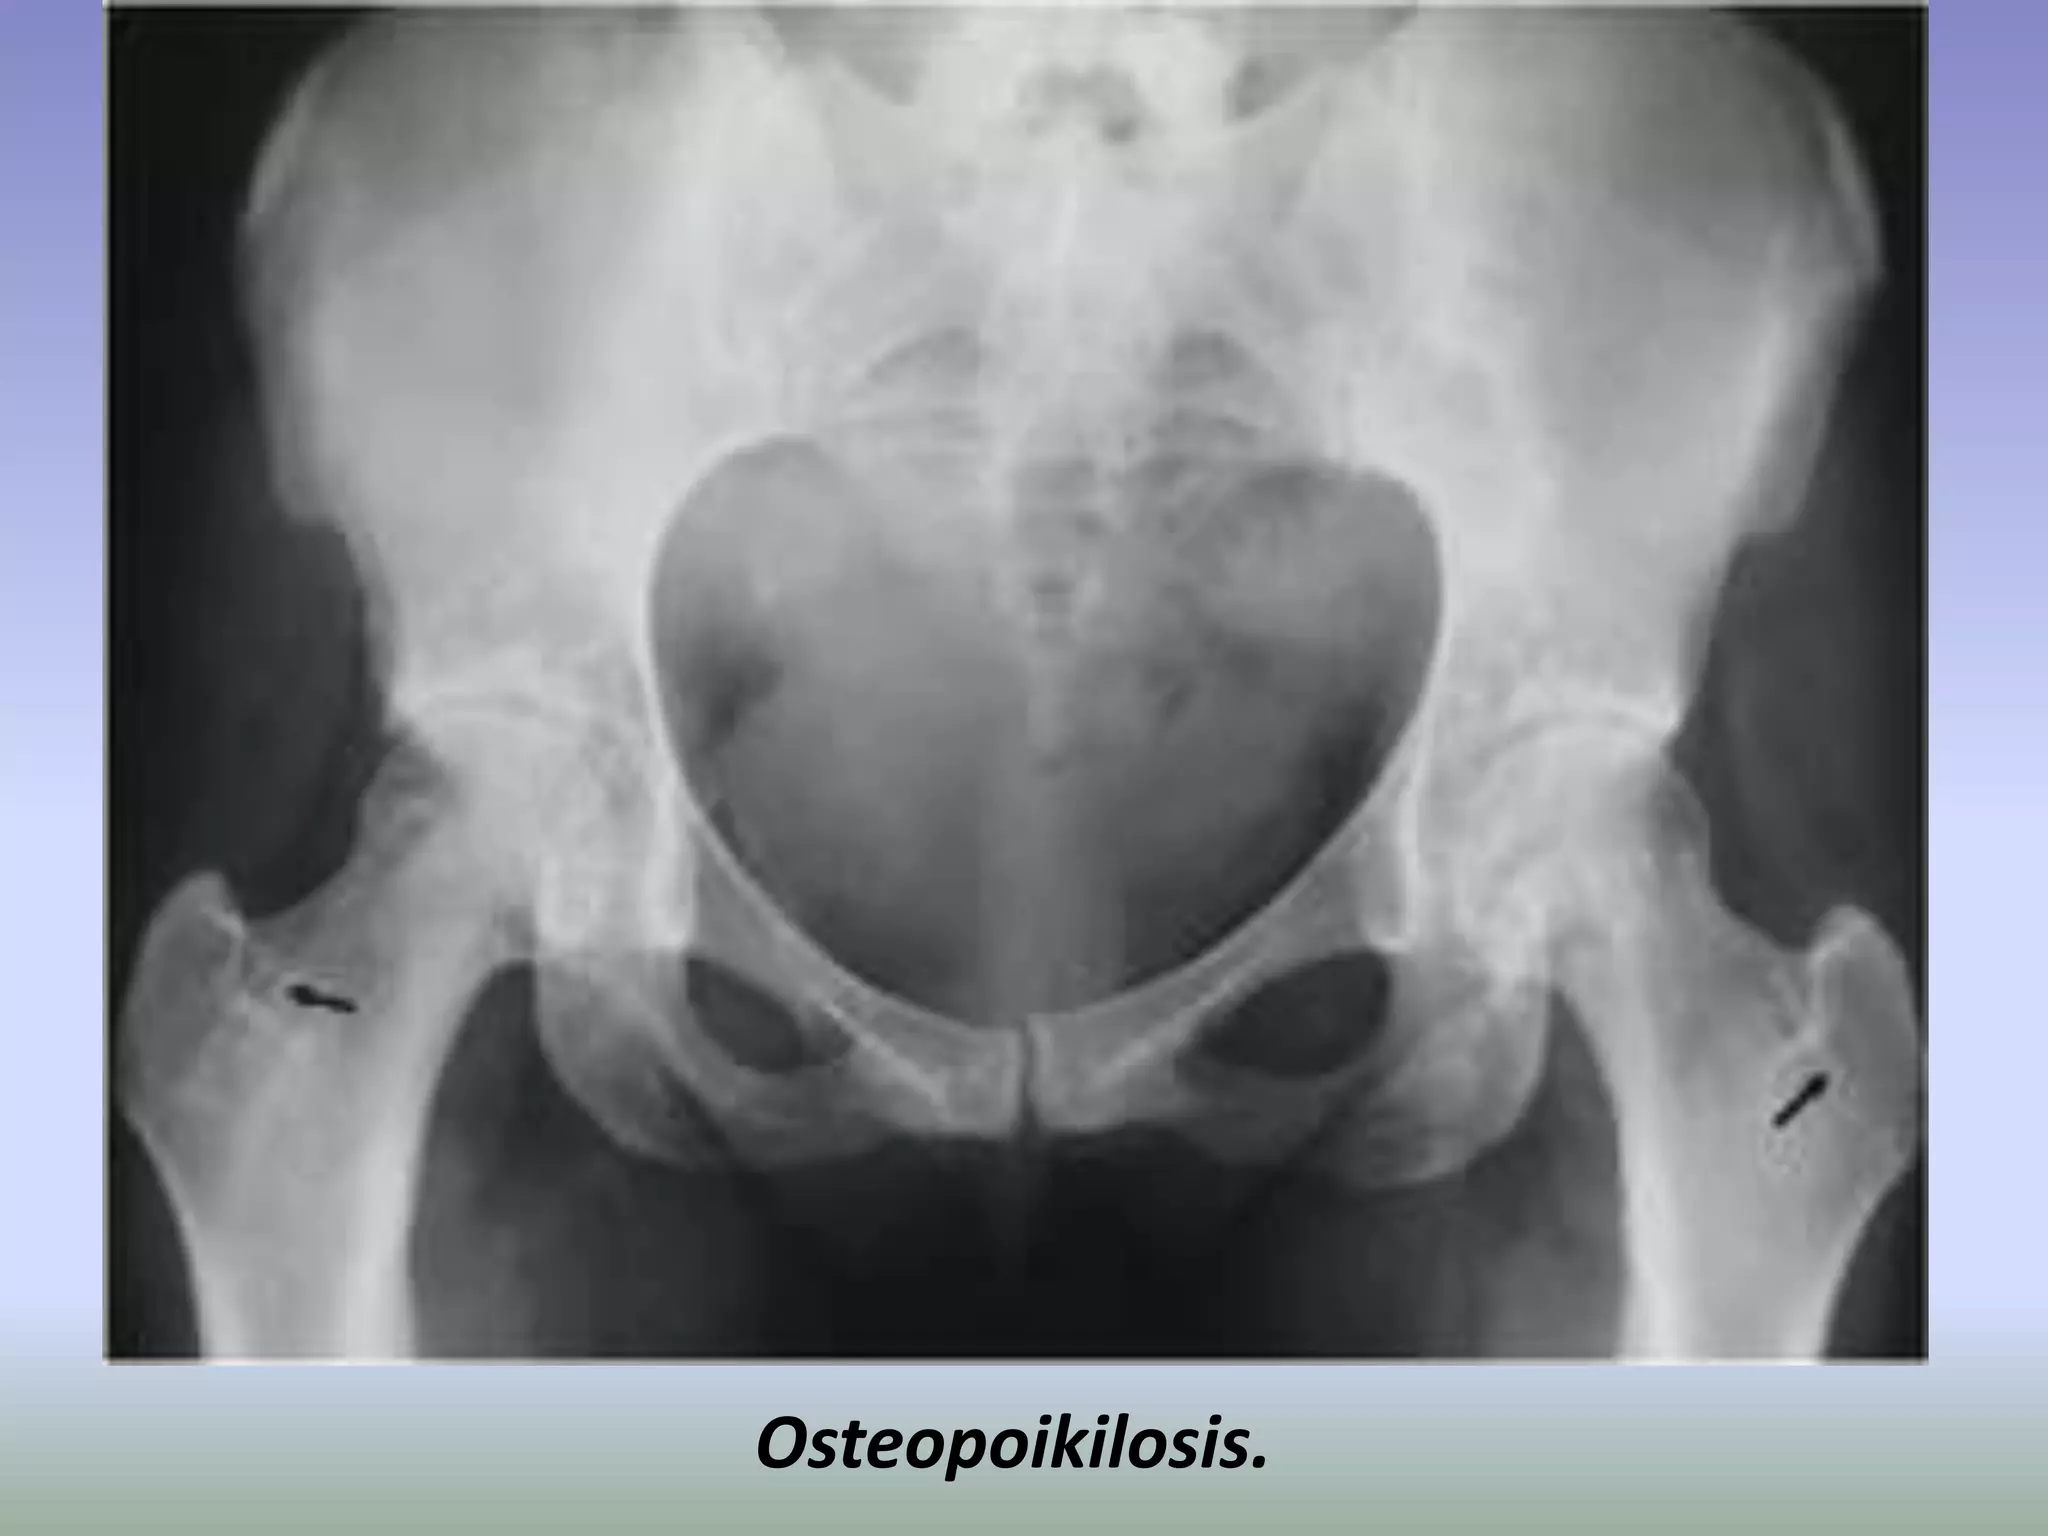

Osteopoikilosis is a benign, autosomal dominant sclerosing

dysplasia of bone characterized by the presence of numerous bone

islands in the skeleton.

The radiographic appearance of osteopoikilosis on an x-ray is

characterized by a pattern of numerous white densities of similar

size spread throughout all the bones. This is a systemic condition. It

must be differentiated from blastic metastasis, which can also

present radiographically as white densities interspersed

throughout bone. Blastic metastasis tends to present with larger

and more irregular densities in less of a uniform pattern. Another

differentiating factor is age, with blastic metastasis mostly

affecting older people, and osteopoikilosis being found in people

20 years of age and younger.

Men and women are affected in equal number. ,reflecting the fact

that this disease attacks indiscriminately. Additionally, the disease

is often associated with melorheostosis, despite the apparent lack

of correlation between Melorheostosis and genetic heritability

Osteopoikilosis.

Osteopoikilosis is abenign, autosomal dominant sclerosing dysplasia of bone characterized by the presence of numerous bone islands in the skeleton. The radiographic appearance of osteopoikilosis on an x-ray is characterized by a pattern of numerous white densities of similar size spread throughout all the bones. This is a systemic condition. It must be differentiated from blastic metastasis, which can also present radiographically as white densities interspersed throughout bone. Blastic metastasis tends to present with larger and more irregular densities in less of a uniform pattern. Another differentiating factor is age, with blastic metastasis mostly affecting older people, and osteopoikilosis being found in people 20 years of age and younger. Men and women are affected in equal number. ,reflecting the fact that this disease attacks indiscriminately. Additionally, the disease is often associated with melorheostosis, despite the apparent lack of correlation between Melorheostosis and genetic heritability